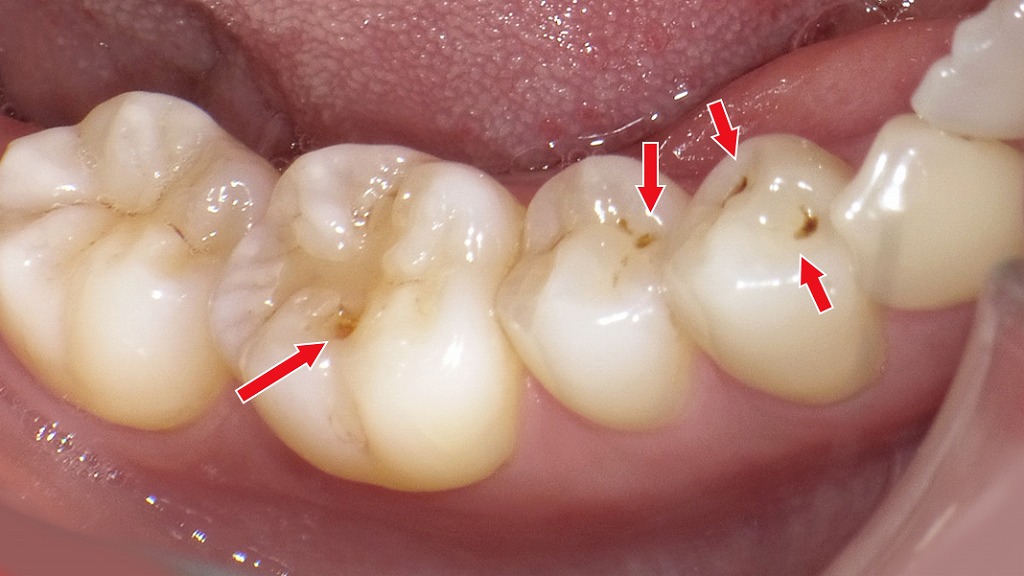

初期虫歯(C1)

初期虫歯(C1)は、虫歯がエナメル質の内部まで進行し始めた段階を指します。まだ穴は大きく開いておらず、痛みやしみる症状が出ないため、自覚しにくいのが特徴です。見た目としては、黒い点や小さな溝の変色として確認されることが多く、歯科医師による診断が重要になります。

歯の黒い点や白濁を見つけた場合、まず行う基本的な診査が**視診と触診(探針での確認)**です。

視診では、歯の色・溝の深さ・光の反射・黒い点の形態などを観察し、虫歯か着色かを判断します。触診では、**探針で溝や黒い部分を軽く触れ、軟化の有無や“引っかかり”**を確認することで、エナメル質が破壊されているかどうかを評価します。

視診・触診で分かること

- 着色汚れか初期虫歯(C0/C1)かの大まかな判別

- エナメル質に穴が開いているか(C2以上)

- 黒い点の位置による虫歯リスクの推定(溝・歯頸部・隣接面など)